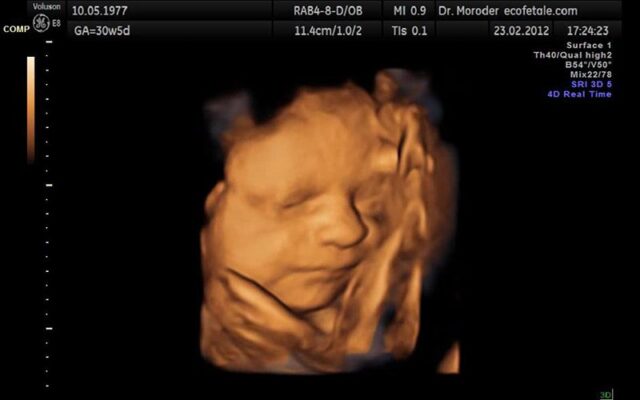

Siêu âm 4D

Siêu âm 4D là một loại siêu âm mới nhất. Và cũng là loại đắt nhất. Nó tạo ra một loại hình ảnh 3 chiều của thai nhi và cho phép quan sát thai trong thời gian thực. Việc sử dụng phương pháp 4D giúp cho các bậc cha mẹ có thể nhìn thấy con của mình hoạt động như thế nào trong tử cung của mẹ. Giúp cho tình cảm của các bậc cha mẹ với con được tăng cường hơn.